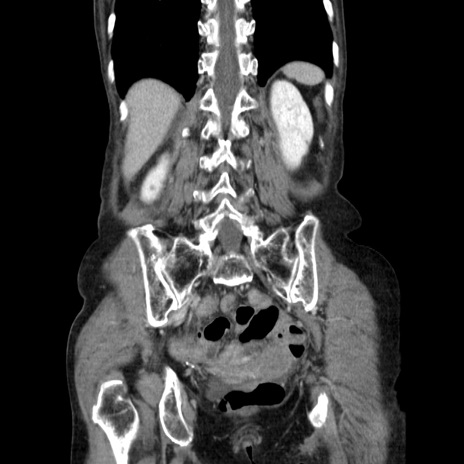

症例25(冠状断像)

【症例】80歳代女性

【主訴】胸のつかえ感

【現病歴】約9時間前に食後から胸のつかえた感じあり、嘔吐あり、来院。

【既往歴】胃癌(全摘)、胆摘、虫垂炎

【身体所見】心窩部に圧痛あり、反跳痛なし。

【データ】WBC 5700、CRP 0.05